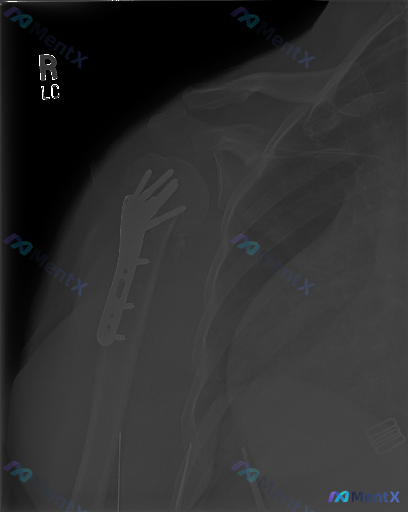

网上看到一张右肩关节正位X光片,资料是右肱骨近端骨折内固定术后复查。

- 右侧肱骨近端可见锁定钢板及多枚螺钉固定,位置尚可

- 肱骨近端骨折线模糊,骨小梁结构重建,未见明显新增透亮线或钢板断裂

- 盂肱关节对位尚可,关节间隙宽度正常

- 肩部周围软组织未见明显异常钙化或积气

影像报告提了“骨折正在愈合或已达临床愈合”,但这份临床分析里还提到了几个容易被忽视的点——比如“没有对比片就不能轻易说愈合良好”,以及“无症状也不能完全排除低毒力感染”。